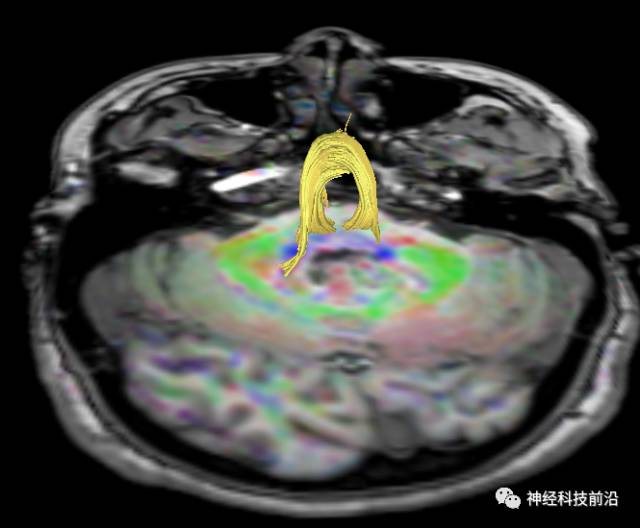

下面为皮质脑桥束的走形方位

皮质脑桥束与脑干高信号(黄色)纤维束